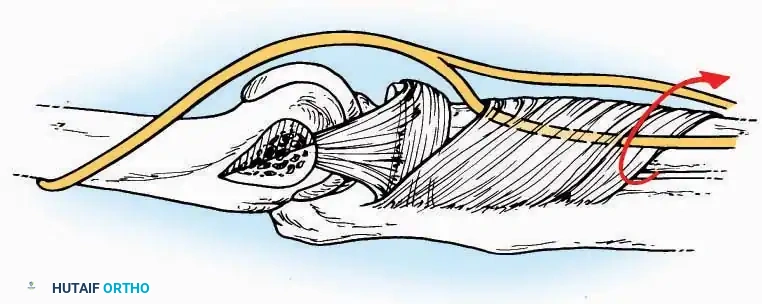

U Approach

Indications: Extensive plantar fasciotomy, radical tumor resection, or complex osteomyelitis debridement requiring access to the entire plantar surface of the calcaneus.

Positioning: Prone, with the leg supported on a large sandbag.

Surgical Technique:

* Incision: Join the medial and lateral approaches described above to form a large, continuous U-shaped incision around the posterior four-fifths of the calcaneus.

* Flap Elevation: Deepen the incision directly to bone. Elevate a massive plantar flap consisting of skin, the specialized fatty heel pad, and the plantar fascia. Retract this flap distally to expose the entire plantar calcaneal tuberosity.

Kocher Approach (Curved L)

Indications: Complete excision of the calcaneus (calcanectomy) for malignant tumors or recalcitrant osteomyelitis.

Surgical Technique:

* Incision: Incise the skin over the medial border of the Achilles tendon, starting 7.5 cm proximal to the calcaneal tuberosity. Extend it distally to the inferoposterior aspect of the tuberosity, curve it transversely around the posterior heel, and continue distally along the lateral surface of the foot to the tuberosity of the fifth metatarsal.

* Deep Dissection: Divide the Achilles tendon directly at its insertion and carry the dissection down to the bone.

* Enucleation: To reach the superior surface, free all tissues beneath the severed Achilles tendon. The calcaneus can then be enucleated subperiosteally or extraperiosteally depending on the oncologic or infectious margins required.